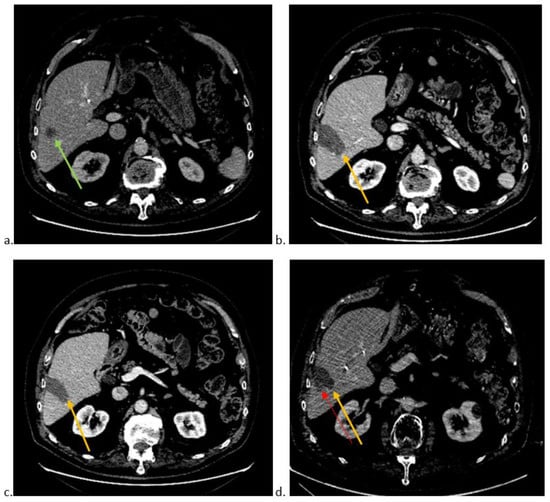

| Size of nearby vessel (mm) | 177 | 1.27 | [1.13–1.45] | <0.001 |

| Distance to vessel with diameter > 3 mm | 177 | 0.59 | [0.44–0.78] | <0.001 |

| Thermoablation site shape (non-ovoid versus ovoid) | 177 | 4.25 | [1.87–9.76] | <0.001 |